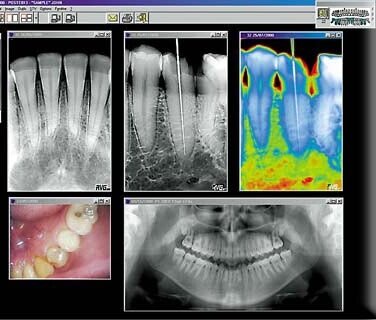

Цифровые снимки на экране монитора

Радиовизиограф из себя представляет комплекс современно усовершенствованного малых габаритов рентгеновского аппарата, который функционально и модульно подключен к компьютеру, с установленным програмным обеспечением. Ставшая в прежние времена традиционной, рентгеновская пленка теперь заменена на специальный сверхчувствительный датчик. Сенсорный датчик под влиянием излучения фиксирует информацию, а затем передает ее на монитор компьютера, на котором воспроизводится визуализация снимка.

Повышение информативности и высокое качество отображения снимков в цветной трехмерной визуализации

Изображение, снятое на радиовизиограф обладает повышенной информативностью, чем может предоставить пленка. Потому что для того, чтобы увидеть сделанный снимок необязательно проявлять, компьютер преобразует информацию с негативной съемки и отбразит на мониторе. Также хранить снимки пациентов очень удобно внеся в единую электронную карту, что значительно облегчает процесс работы. Снимок с визуализированной инфорацией вносится и сохраняется в электронной базе данных, к которым имеется доступ у лечащего врача. В настоящее время очень важной является возможность моментально передавать диагностические данные с компьютера специалиста до любой точки земного шара по сети Интернет.